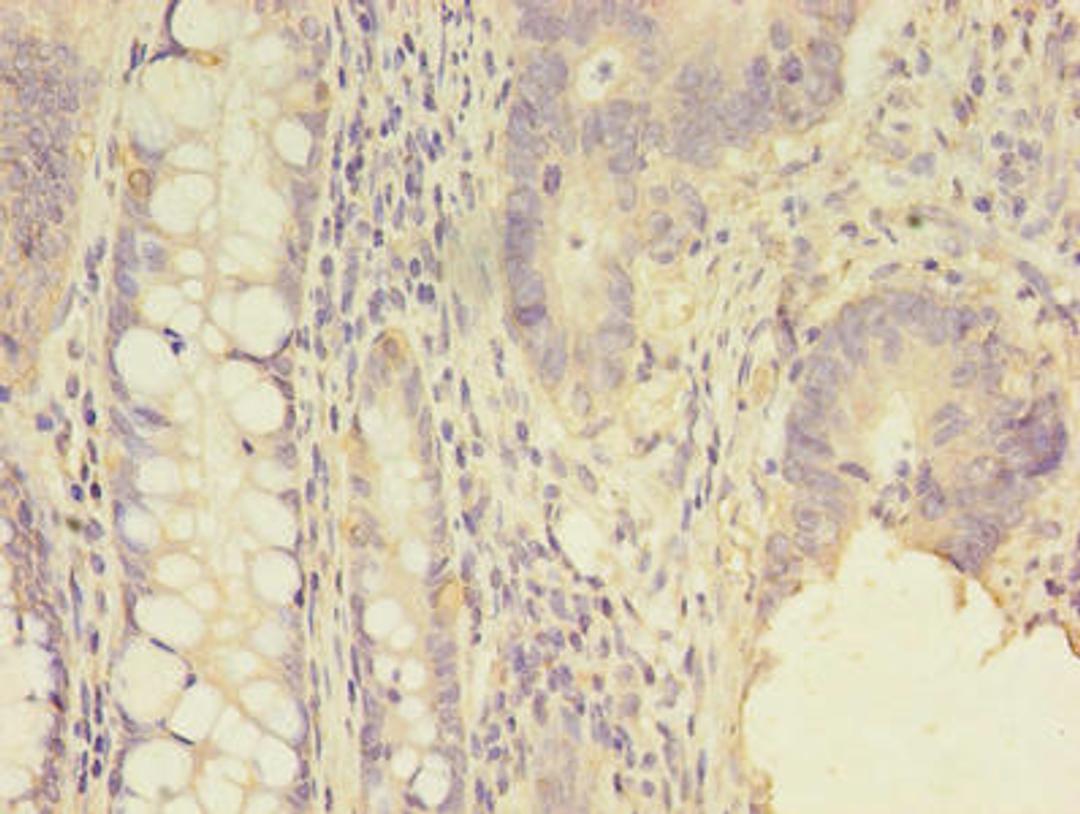

SCNN1G Antibody

• Immunohistochemistry (IHC)